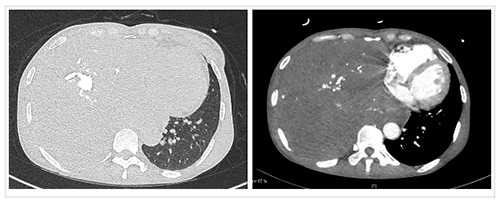

患者入院后复查胸部强化CT,结果显示右侧胸腔见巨大混杂密度团块,增强扫描动脉期病灶内见多发迂曲血管走行;纵隔明显左偏。患者胸腔瘤体巨大,国内外均较为罕见。不仅如此,由于长时间的肿瘤消耗,患者处于严重营养不良状态,白蛋白24.5g/L,血红蛋白89g/L。而且,患者右侧肺组织长期不张,肺功能FEV1仅有0.86L,MVV仅有23.78L/min,提示极重度混合性通气功能障碍。